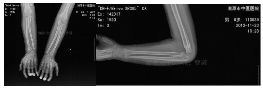

外院片如下:

入院后行四步复位法整复骨折,小夹板外固定,拍片复查

伤后近一个月拍片复查见骨痂生长明显

伤后两个半月拍片复查